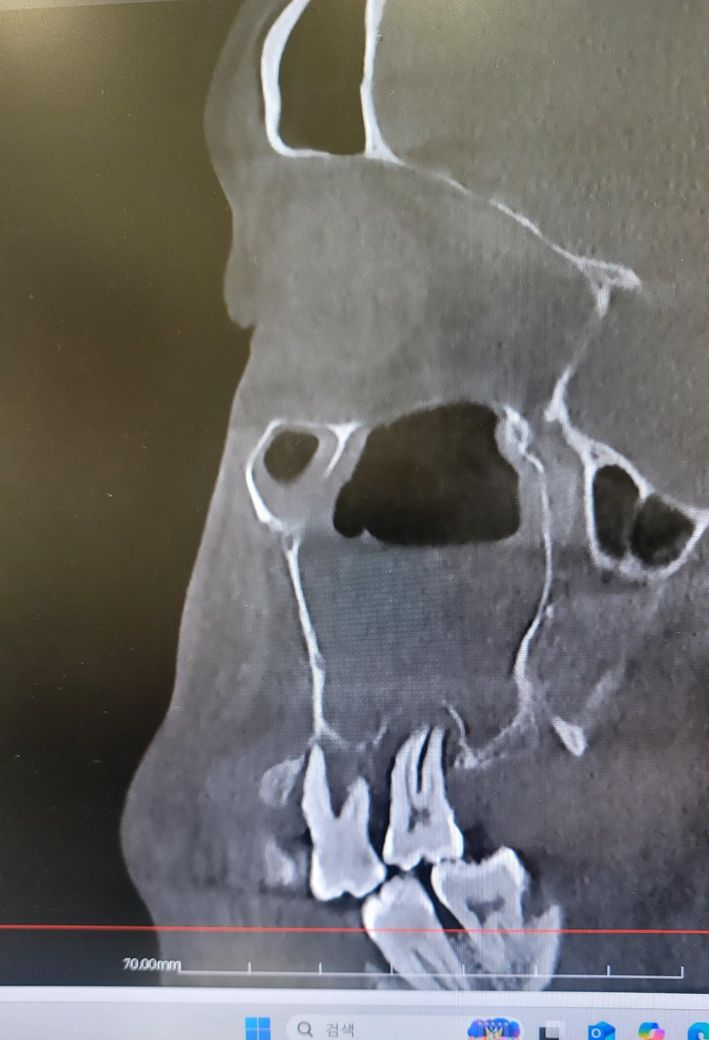

CT를 보시더니 한쪽에 부비동염 농이 차있는데 이로인해 두통이 오는거였고 이게 원인이 치성 부비동염 같다면서

오른쪽 어금니를 보시고는 치아 뿌리에 염증이 있어서 치아 뿌리가 녹아서 부비동염이 온 것 같다며 치과를 가셔서

• 1번 째 사진

치아떄문에 생긴 상악동 염증이라면 발치를 하시고 나서 상악동의 염증도 같이 제거를 하시는게 좋을것같습니다. 이미 잇몸뼈가 많이 소실된 상태 같습니다.

사진으로 봤을 경우 치아 주변의 치조골이 이미 손실된것으로 보입니다.

치아를 지지하고 있는 치조골이 손상되면 치아를 살리지 못하는 경우가 많기 때문에 발치를 하게 됩니다.

2. 상악동 염증이 꽤 크네요. 이게 치성원인이라면 발치는 불가피하고 발치 후 상악동 세척술 필요합니다.

3. 이미 치아와 상악동 부위는 개통되었을 것 같네요. 발치 후 천공이 문제가 아닙니다.